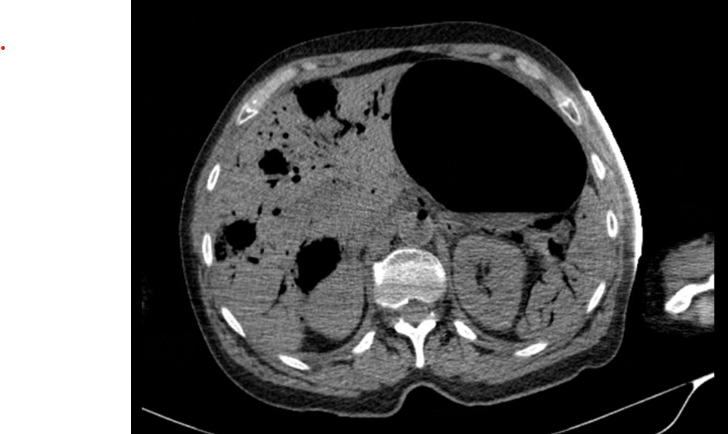

Figure 2: Air in the lumen of multiple vascular structures.

The figure 2 shows the presence of air in the lumen of the middle and left hepatic veins, with gaseous content in multiple vascular structures with a branched appearance in both lobes of the liver and gaseous structures/collections with multiple millimetric air bubbles in the liver parenchyma that communicate with the vascular structures; we can also see air in the vessels of the splenic hilum and intrasplenic vascular structures.